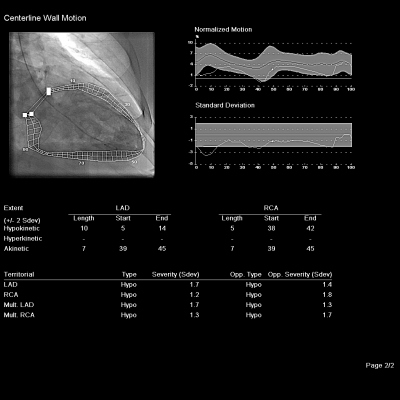

Sedmašedesátiletý muž byl v listopadu roku 2017 vyšetřen v katetrizační laboratoři Pracoviště invazivní a intervenční kardiologie Interní kardiologické kliniky FN Brno pro tři měsíce trvající progresi námahové dušnosti do funkční třídy NYHA III, nový záchyt fibrilace síní, přechodných depresí úseku ST v inferiorních svodech a echokardiografický nález systolické dysfunkce levé komory s globální hypokontraktilitou akcentovanou v oblasti baze dolní stěny a s celkovou ejekční frakcí levé komory 40 %. Koronarografie odhalila významnou stenózu ramus interventricularis anterior (RIA) levé věnčité tepny s angiografickou redukcí lumen přibližně 70 % a chronický uzávěr pravé věnčité tepny (arteria coronaria dextra, ACD) s dobře patrným kolaterálním zásobením z levé věnčité tepny (obr. 1–3 a video 1–3).

Rozsah koronárního postižení odpovídal střednímu rozsahu s hodnotou SYNTAX skóre II 20 bodů. Pacient byl dlouhodobě léčen jen pro hypertenzi a má nadváhu (body mass index 29,7 kg/m2), jinak je bez významných rizikových faktorů aterosklerózy. Postižení obou tepen bylo hodnoceno jako vhodné ke katetrizačnímu ošetření a po diskusi s pacientem byla na leden 2018 naplánována elektivní koronární intervence (PCI). Plánovanému zákroku předcházelo zahájení podávání duální antiagregace (kyselina acetylsalicylová v dávce 100 mg denně a clopidogrel 75 mg denně). Výkon byl proveden za použití dvou arteriálních přístupů. Do ústí pravé věnčité tepny byl zaveden katétr Vista JR4 7F (Cordis – Cardinal Health, USA) cestou pravého femorálního přístupu, do ústí levé věnčité tepny pak zaváděcí katétr Vista XB4 6F (Cordis – Cardinal Health, USA) pravým radiálním přístupem (obr. 4 a video 4).